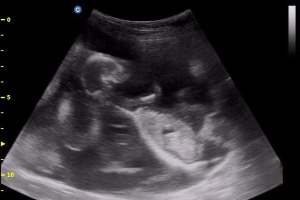

Topics will include: nutritional management, use of ultrasound, facility design, newborn care, hypothermia treatment, grafting, vaccination protocols, mortality diagnoses, health and feeding program assessment.